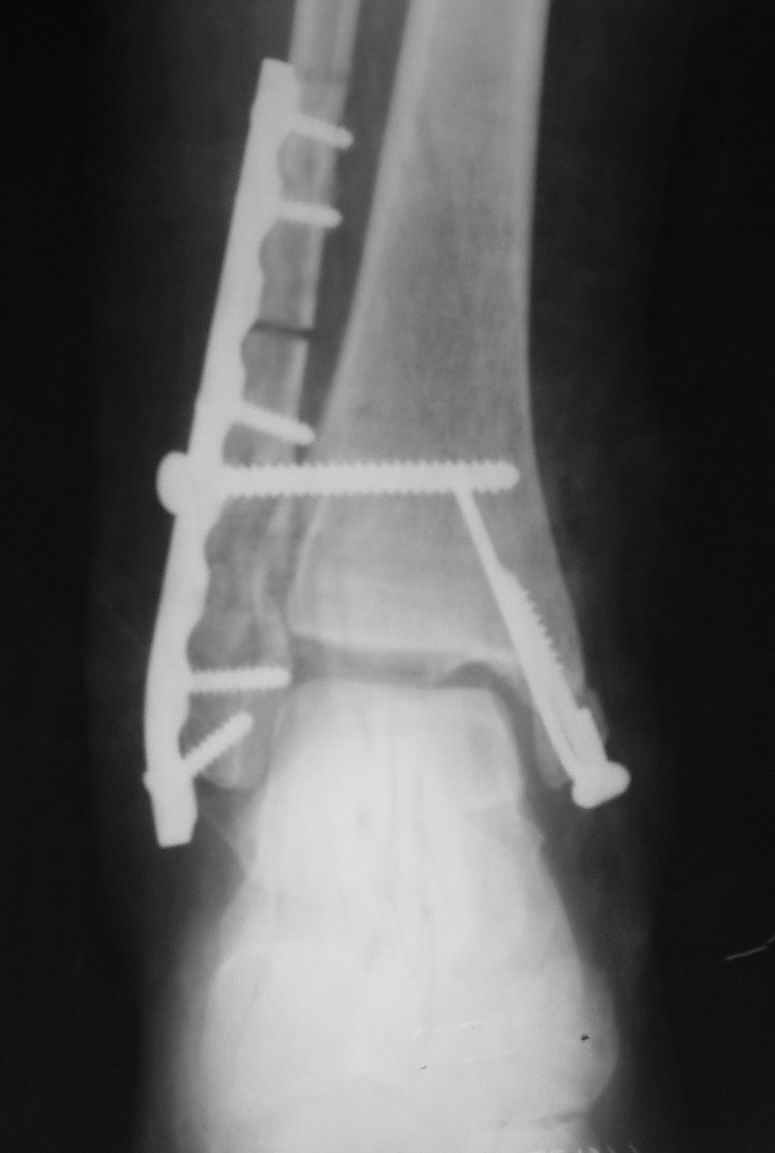

Уважаемые коллеги! Персонально, дорогой доктор Джолдас. Не знаю, почему почта к тебе не проходит - у меня почтовая программа "Bat", снимки в JPG. Выставляю через форум. 10 апреля я показывал снимки больной с застарелым переломо-вывихом голеностопного сустава. 9 июня прооперировал, снимки прилагаю. R-контроль через месяц ходьбы на костылях, все стоит также. Разрешил частичную (20кг) нагрузку на ногу, пока жалоб нет.

Ход операции - сагиттальная остеотомия по линии неправильно сросшегося перелома малоберцовой кости, остеотомия с формированием внутренней лодыжки, попытка вправления подвывиха неудачна из-за того, что "не хватало" длины малоберцовой. Остеотомия малоберцовой кости выше синдесмоза. Остеосинтез.